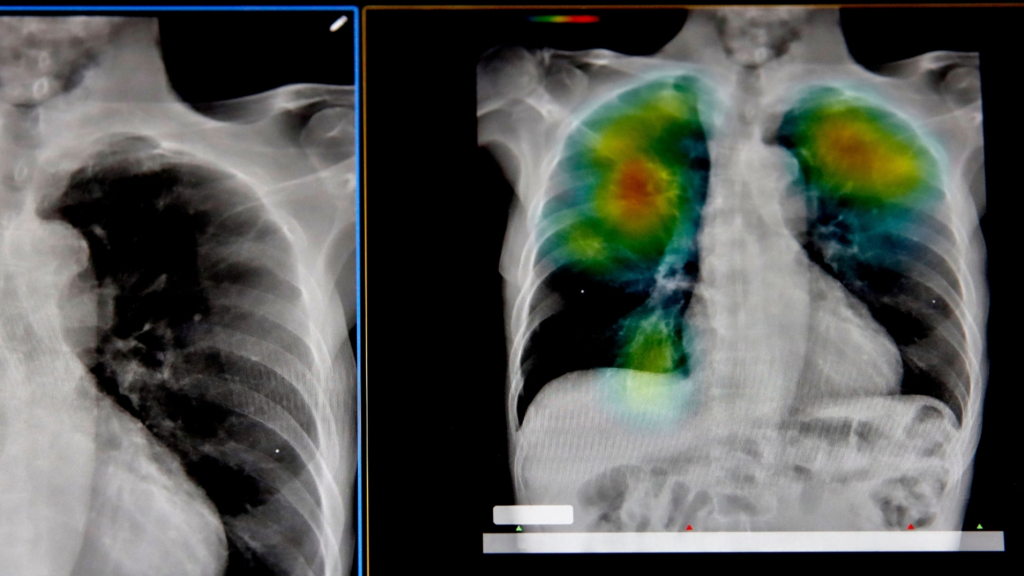

It’s an approach adapted from something called the dynamic network biomarker theory. It suggests that as the body approaches disease, certain molecular networks begin to fluctuate and become more connected than normal. In studies of influenza, for example, these patterns begin to emerge days before symptoms appear. In cancer research, they identified similar signals that appear around the point where cells begin to turn malignant. The prediction accuracy of these patterns is somewhere over 80 percent.

There are still plenty of hurdles to overcome before we reach the point where AI predicts a tumor long before symptoms appear. The system is heavily dependent on a constant stream of clean data. Without it, or even just with large gaps, the system can trigger all sorts of false alarms and detect correlations that don’t actually have a real causal relationship. And there’s also the vexing issue of AI hallucinations, known in the medical world as a black box, which is when an AI model spits out a prediction that even its own designers can’t explain.